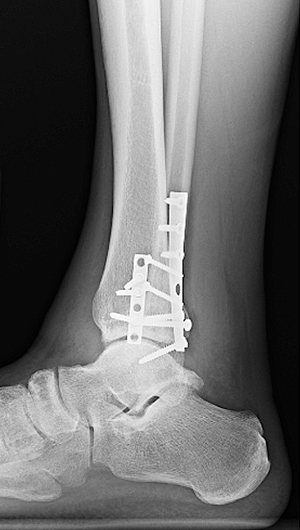

Treatment of a broken leg depends on the location and severity of the injury. A severely broken leg may require surgery to implant devices into the broken bone to maintain proper alignment during healing.

You might need surgery to repair a fractured leg, especially if you break your femur. Some people can recover without surgery and only need a splint or cast. You’ll need physical therapy to regain your leg’s strength and ability to move..